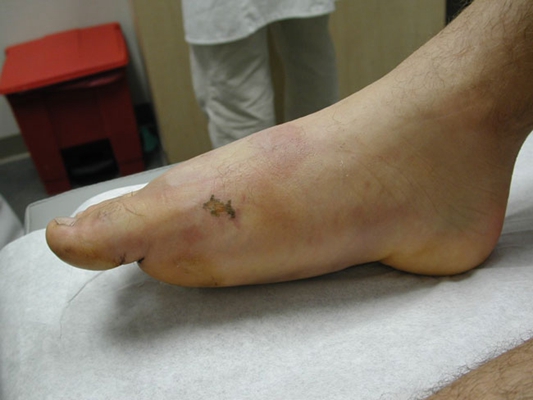

骨癌圖片

骨癌